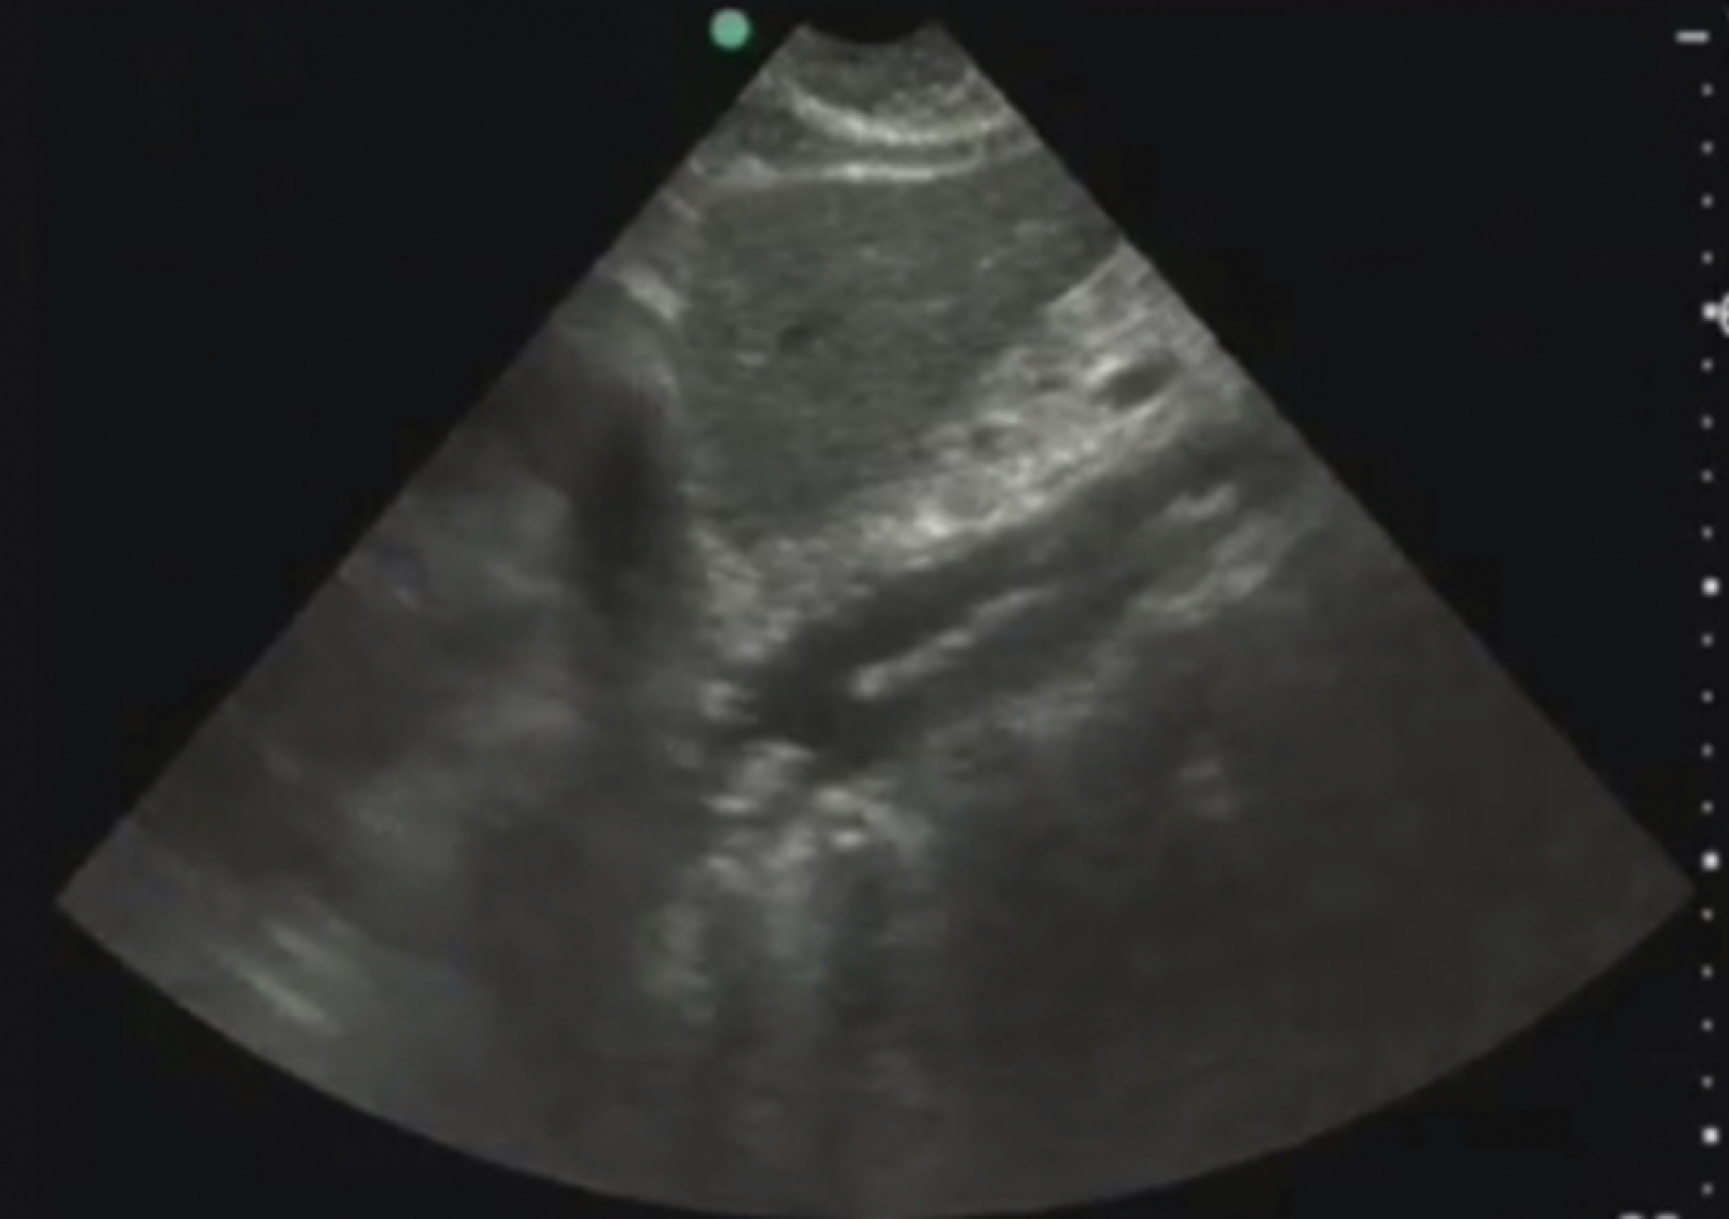

Pathology

Hydronephrosis is characterized by dilation and anechoic fluid accumulation within the renal pelvis and calyces, ranging from mild to severe ( Fig. e3.6 ). Renal and/or ureteral calculi may be identified as echogenic foci with associated shadowing and are usually located within the kidney (nonobstructive) or in the renal pelvis, proximal ureter, or uretero-vesicular junction. Color Doppler placed over the kidney can help differentiate mild hydronephrosis from the renal vasculature, as well as possibly accentuate any renal stones by producing the renal twinkle artifact.

Hydronephrosis with dilation of the calyces and renal pelvis of the kidney showing thinning of the cortex, signifying severe hydronephrosis.